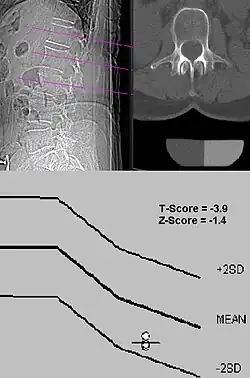

Die verschiedenen Methoden und Geräte sind nicht untereinander vergleichbar. Darum sollten im Befund keine absolute Dichte (außer in der qCT oder pQCT) oder Flächendichte angegeben werden, sondern die Abweichungen vom (geschlechtsspezifischen) Normalen in Vielfachen einer Standardabweichung (als sogenannter t-Wert, engl. t-score).

Nach der gültigen Definition der WHO liegt eine Osteoporose vor, wenn der Messwert der Knochendichtemessung mindestens 2,5 Standardabweichungen unter dem Durchschnitt der geschlechtsgleichen 30-jährigen Gesunden (peak bone mass) liegt, d. h., ein t-Wert ≤ –2,5 vorliegt. Zwischen –1 und –2,5 Standardabweichungen wird von einer reduzierten Knochendichte, einer Osteopenie, gesprochen. Ab einem t-score Wert von −2,6 liegt eine deutlich reduzierte Knochendichte vor und es besteht eine erhöhte Knochenbruchgefahr Osteoporose.

z-Wert

Neben dem Bezug des t-Werts auf die peak bone mass einer jungen Vergleichspopulation wird oft der z-Wert angegeben, der einen Vergleich mit einer Population desselben Alters ausdrückt, ebenfalls als Angabe der Standardabweichungen unter dem Mittelwert.